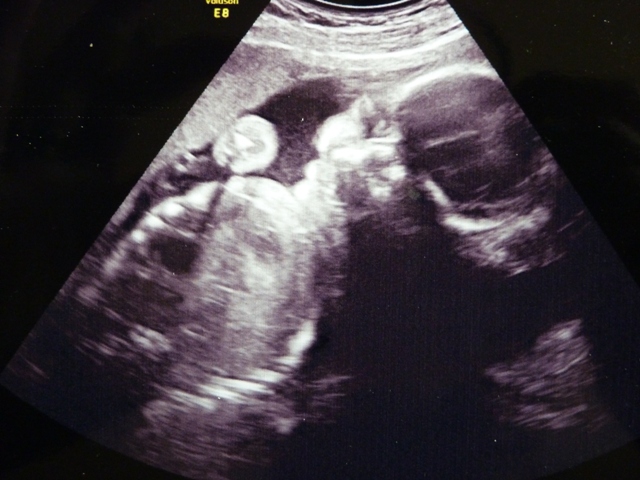

v úterý jsme byly na kontrole, vše je v pořádku, tak přikládám také fotku, zase mazaninu Sofinky a můj buben

Poslední týden v 2.trimestru, holky to letíííí...už jen 95 dní do porodu...UUUf. A mojí porodní asistentce se dnes narodila holčička Jasmínka Viktorie

Jo a Hermi ty fotky, máte nádherného chlapečka

to je neskutečný,jak to ta technika dokáže zachytit. Já se na tu naši "žabku" tak těšííím. Taky se necáváme překvapit, jak psala Zori, takže jsme 3D vynechali a hrozně se těším,až ji budu mít u sebe...